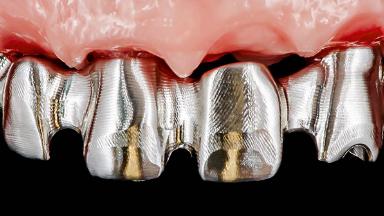

Rehabilitating an Edentulous Maxilla with a Fixed Dental Prosthesis Following Provisional Immediate Loading

This case features the flapless computer-guided placement of 7 bone-level implants, distributed to provide maximal support for the prosthetic framework. A rigid one-piece metallic framework was utilized as an interim restoration to reduce the risk of fracture associated with this prosthetic design. As part of the clinical examination, the SAC Assessment Tool was used, resulting in a surgical and restorative risk classification as “complex”.